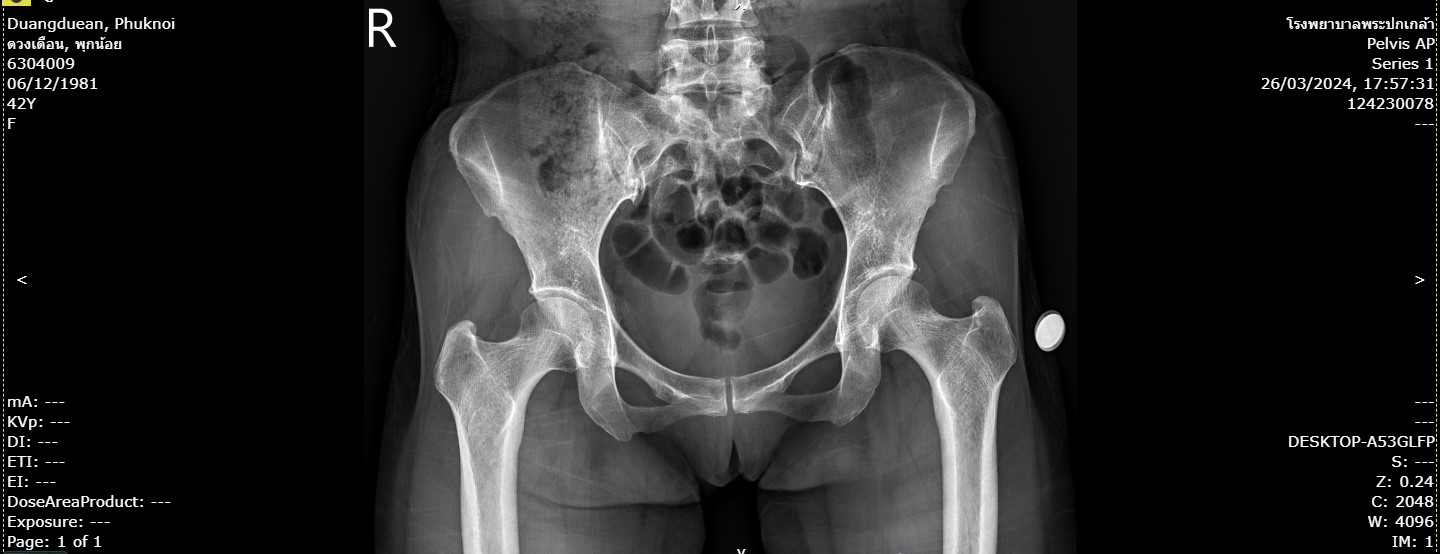

87ดวงเดือน.jpg                     17-Apr-2024 06:43              127070